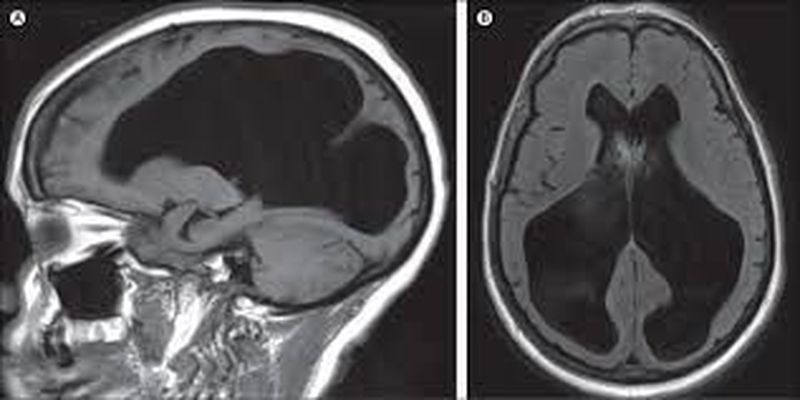

Hydrocephalus is a condition in which an accumulation of (CSF) occurs within the brain.